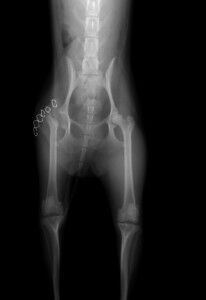

実際の手術後の写真が下の写真です。

右脚の大腿骨頭が無くなっているのがわかります。